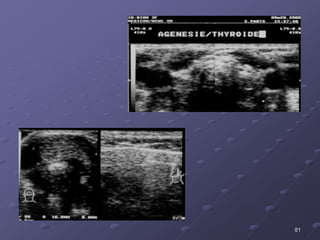

 Voâ saûn hoaëc laïc choå

tuyeán giaùp.

 Thieåu saûn 1 thuøy.

II. DÒ DAÏNG BAÅM SINH: